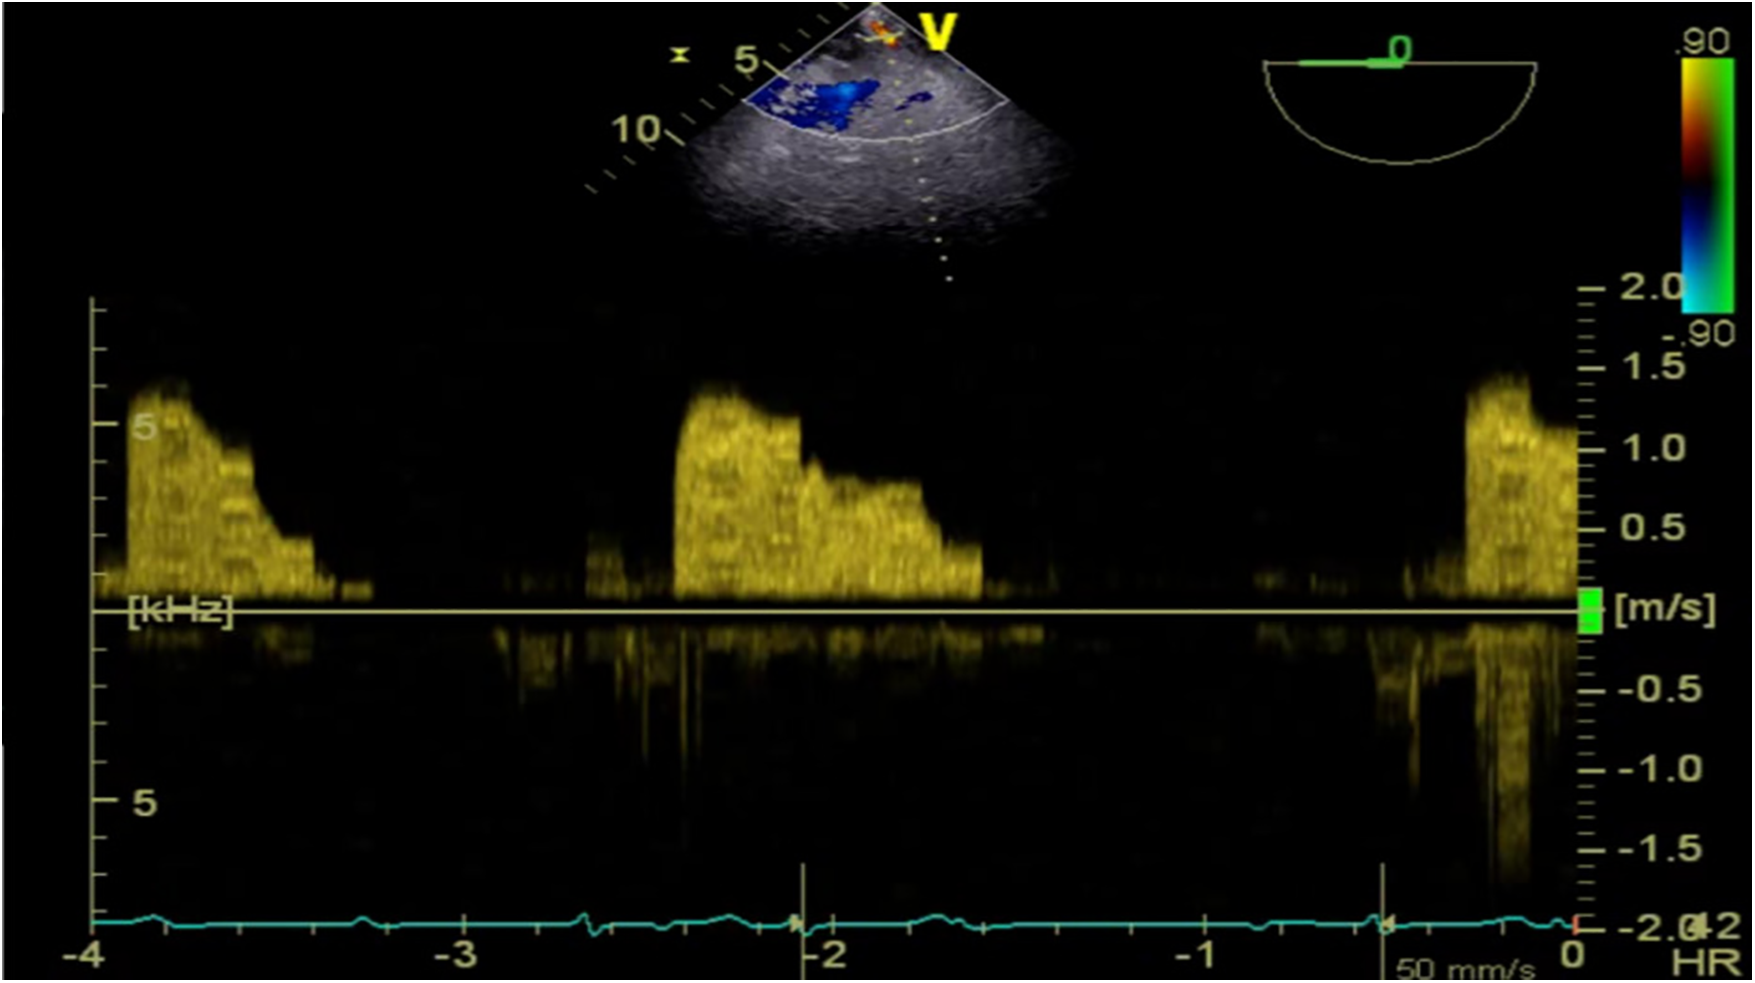

Given this emergent situation, cardiopulmonary bypass was reinitiated to resolve the circulation crisis. The results of TEE monitoring showed that the left atrial dissection hematoma was compressing the left ventricular inflow tract, which accelerated blood flow through the mitral valve, causing mitral valve relative stenosis. In addition, TEE found pulsatile blood flow in the hematoma at the left atrioventricular groove on the posterior wall of the left atrium after the second cardiopulmonary bypass (Figure 2), suggesting that this blood flow was related to the left coronary circumflex branch. However, the relationship between the left circumflex branch and the dissection could not be determined. Because the criminal's blood flow (blood vessels) was located in the posterior atrioventricular groove and could not be explored through a surgical incision, we ultimately decided to incise the left atrial endocardium to drain the decompression hematoma through the left atrium (Figures 3, 4). The specific method applied was to reopen the right atrium and atrial septum along the original surgical incision. After confirming the correct position of the artificial valve and the integrity of the left atrial endocardium, the latter was incised for drainage and decompression, and the atrial septum and right atrium were resutured. The patient was admitted to the ICU for further management and discharged home after 16 days.

Figure 2. TEE detected pulsatile blood flow in the hematoma located at the left atrioventricular groove on the posterior wall of the left atrium.